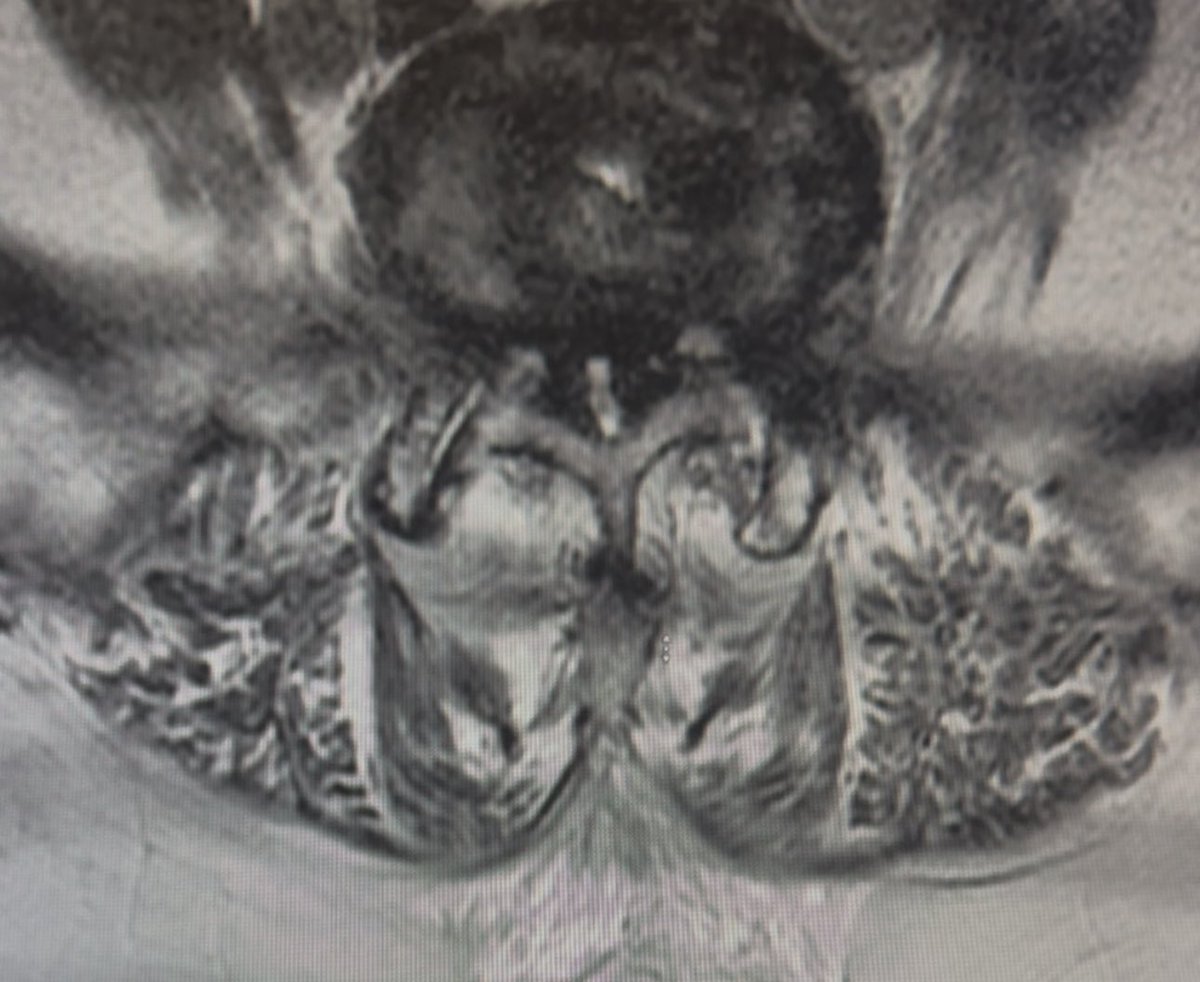

الوقايه خيرٌ من العلاج. مراجعه لأشعة الرنين المغناطيسي ( للعمود الفقري) لمريض لم يصل الى الستين من عمره اتى للعيادة يشتكي من ألم الظهر المزمن. الاشعة تبين الحالة المرضيه للعمود الفقري من انزلاق غضروفي ، احتكاك مفاصل ، تضخّم الأربطة ، انحسار القناه الشوكيه، تضيق جذور الاعصاب